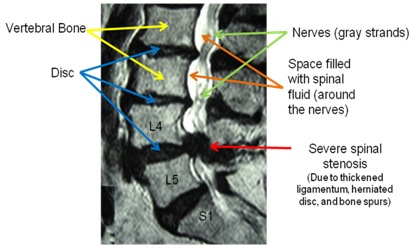

What is “spinal stenosis?”

Spinal stenosis simply means narrowing of the spinal canal. There are two types of spinal stenosis:

- Degenerative – MOST COMMON TYPE occurs slowly over time as we get older and described below

- Acute – occurs relatively quickly as a result of an injury or acute disc herniation

The MRI demonstrates severe spinal stenosis in between the L4 and L5 bones. Note that there is no white fluid (space) around the nerves at that level. In fact, there is no space around the nerves and they are completely “pinched!”